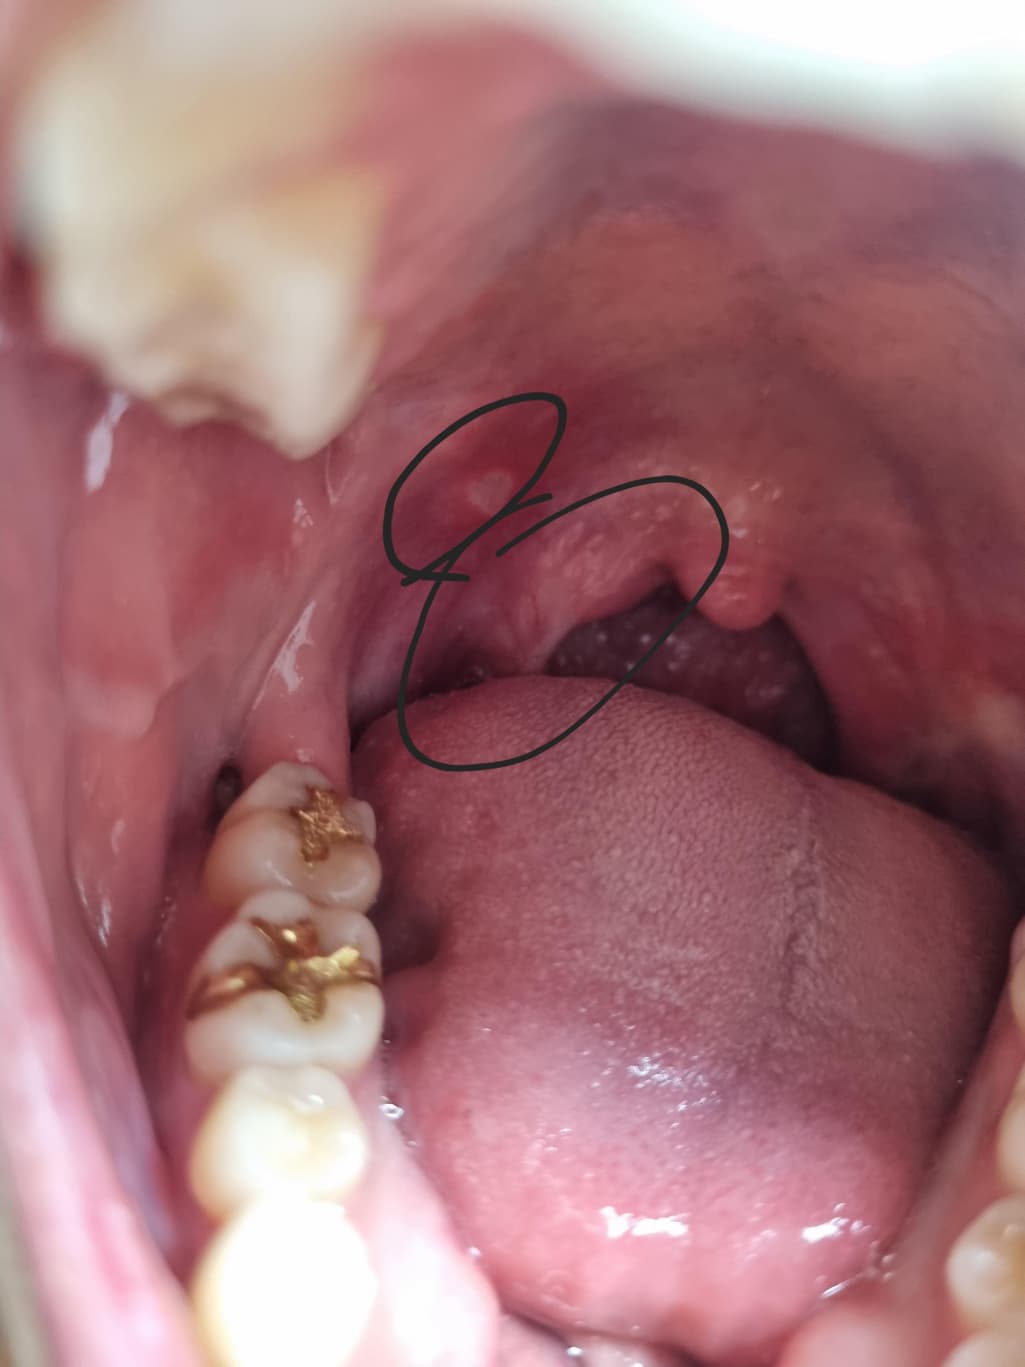

한3일전부터 동그라미 친부분이 조금 불편해서 사진으로 찍어보니 구내염이있는것같고 목젖쪽은 잘모르겠는데 불편하고 살짝 아픕니다. 심각한건가요? 아니면 영양제잘챙겨먹으면 호전될까요?

올려주신 사진이 또렷하지 않아 목젖 주변은 잘 확인되진 않으나 바깥쪽 표시 부위에서 구내염 소견이 관찰됩니다.

충분한 휴식과 영양 섭취만으로도 회복이 가능하나 통증이 심한 경우 구내염 연고를 바르고 회복을 지연 시킬 수 있는 음주, 흡연, 자극적 음식의 섭취를 피하기 바랍니다.